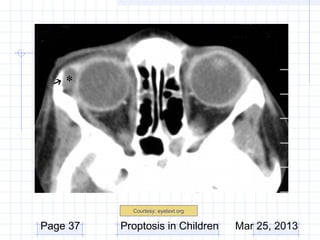

Work-up

CT/MRI

– Indicated if posterior extent not palpated

– Cystic appearance

– Well circumscribed lesion

Courtesy: eyetext.org

Page 37   Proptosis in Children     Mar 25, 2013